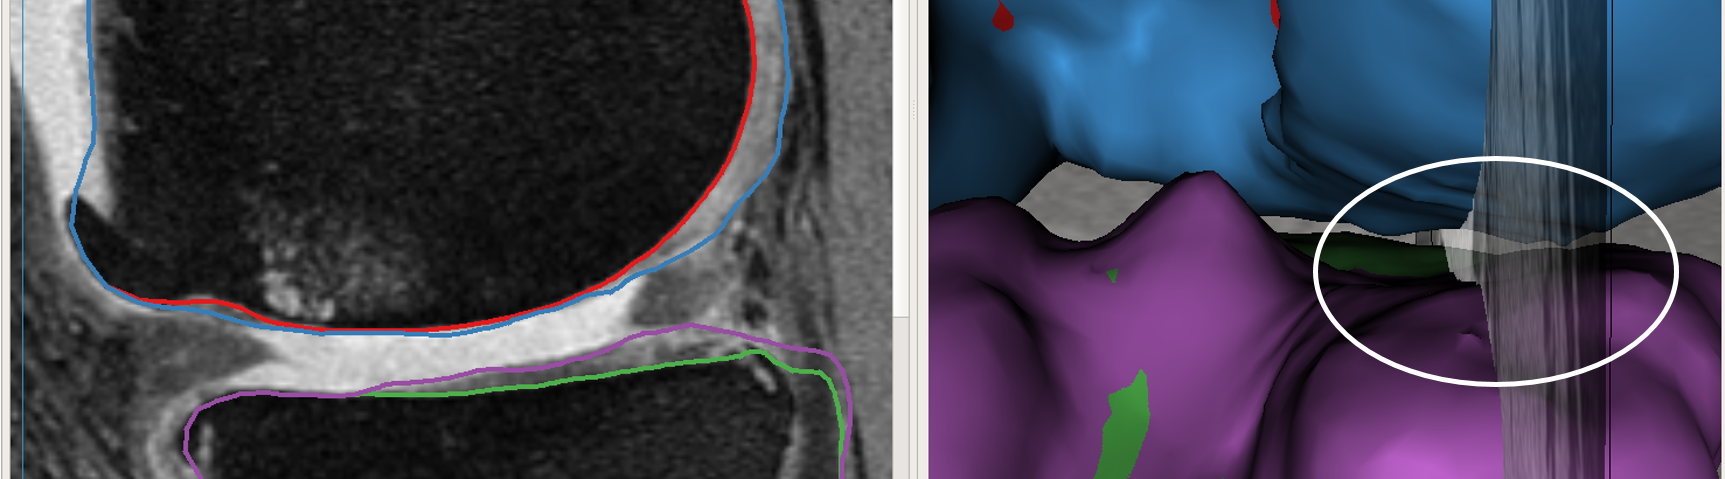

User provided nudge points: The user identified correction is provided as a set of nudge points which guide the segmentation to the correct position. Fig. 3a shows the GUI magnified with the volume and the automated LOGISMOS segmentation results overlayed. The particular slice indicated is a case with severe OA having bright fluid regions improperly segmented as cartilage. The blue line with points are the nudge points indicated by the user approximately identifying the correct cartilage region.

Max-flow re-computation: Following the local graph cost modification the max-flow is recomputed in 3D within a few milliseconds and the updated surfaces rendered onto the GUI. As seen in Fig. 3b the correction made by the nudge points are reflected in the updated cartilage surface overlayed on the image volume.

The above work-flow is repeated to correct the tibial cartilage errors as well. In the intermediate steps following the correction of the femur, the tibia bone and cartilage surfaces appear to worsen. This can be attributed to a combination of the existing graph costs and the graph constraints. Since the tibia cartilage surface has no clear defined edge cost in that region, the surface result moved along with the femur corrected cartilage surface. Subsequently due to the inter-surface distance constraints between the tibial surfaces the tibial bone surface also changed. However once the nudge points provided the appropriate locations for cost modification the erroneous surfaces were corrected (Figs. 3c,d). Note that the corrections made on a single 2D slice resulted in the entire locally affected 3D neighborhood being corrected. This can be appreciated in the corresponding circled regions of the surface model.